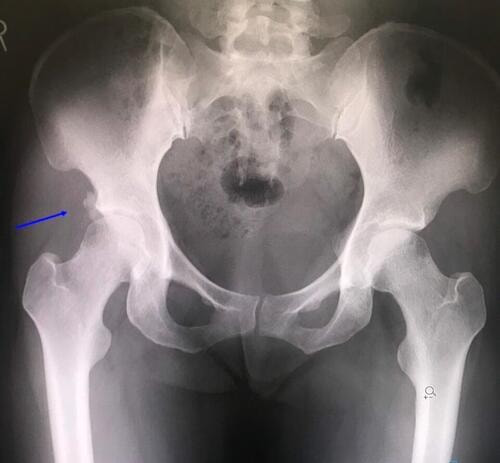

レントゲン検査の結果「軽度の股関節臼蓋不全」及び「石灰沈着」を確認。

石灰沈着は骨盤の下前腸骨棘付近に存在し、下前腸骨棘には大腿直筋が付着します。

こちらの患者様、大腿直筋が作用する動作にて、著明に痛みが出現するため、

今回の痛みは石灰沈着が原因で出現していたと判明。